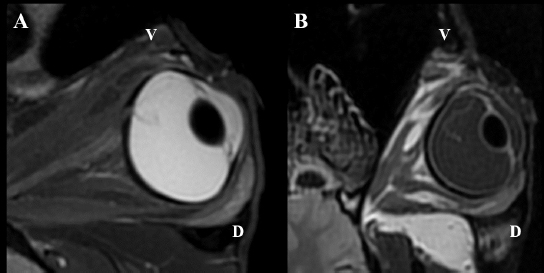

Following euthanasia, MRI of the heads was performed, using a high field (1.5T) system (GE, Signa Explorer, GE Healthcare, Wauwatosa, WI). T1, fluid-attenuated inversion recovery (FLAIR), and T2 sequences in the sagittal, frontal and transverse planes were acquired. T2 sequences were also acquired in an oblique plane, in the axes of the ONH of each eye.

Intraocular lesions found on US and MRI of both horses were consistent with the ophthalmic examination. Complete RD OS and hyperechoic vitreous floaters OU were noted on US (Fig. 4). RD was also evident OS on MRI, more conspicuously on T2W and FLAIR sequences. In T2 sequences, the detached retina was identified as a V-shaped membrane of intermediate signal inside the hyperintense vitreous and reaching the optic disk (Fig. 5A), while it was slightly hyperintense in comparison to the hypointense vitreous chamber on FLAIR acquisitions (Fig. 5B). There was a subjectively abnormal positioned optic disk OU on US and MRI, suggesting ectopic ONH. OS was flattened at the level of the ONH in both horses. Except for a subarachnoid emphysema due to postmortem changes, the brain looked otherwise normal on MRI. Based on US, the axial globe length measured 39.2 mm OS and 41.5 mm OD of case 1 and 45 mm OU in case 2.

Fig. 5. MRI OS, case 2. T2W oblique plane image highlighting the hypointense-detached retina reaching the optic disk and in direct continuity with the optic nerve. Note the hyperintense periphery of the optic nerve, corresponding to the normal thin layer of cerebrospinal fluid surrounding it (A). FLAIR frontal plane image showing the difference of signal between the slightly hyperintense retina within the hypointense vitreous chamber (B). D: dorsal; V: ventral.